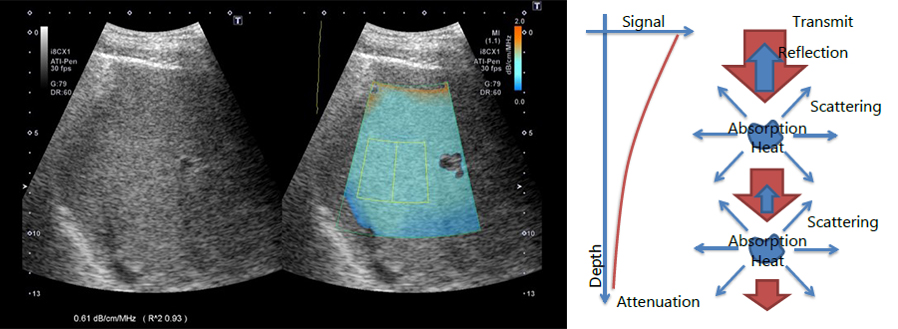

Загасання (Attenuation)

Забезпечує можливість кількісного визначення і колірного кодування змін коефіцієнта загасання в печінці, які можуть виникнути при змінах в складі печінки (наприклад, при підвищенні рівня жиру).